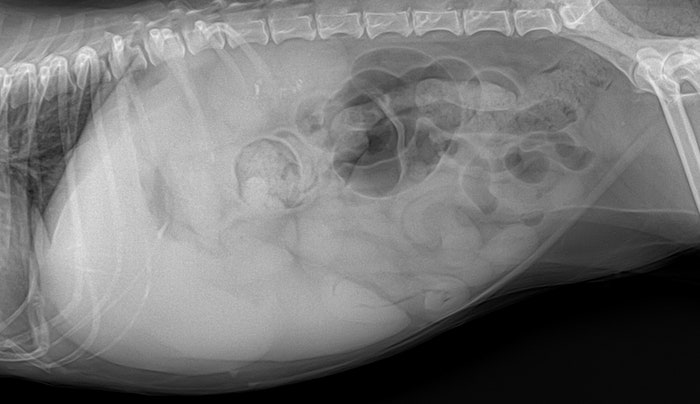

지금부터는 애완동물의 간종양에 대해 말씀드리겠습니다.오늘 얘가 보인 증상이 뭐였을까요?증상 : 구토, 최근 구토가 심하여 동물병원에 내원하게 된 아이입니다.아이가 구토하는 원인을 찾기 위해 검진을 하던 중 종괴가 발견되었습니다.지금까지는 위장관 관련 진료만 받았대요.오늘은 좀 더 자세한 검사를 해봤습니다.강아지 간종양 검사 간종양 검사는 1차적으로 초음파를 통해 확인할 수 있으며, 간종양으로 의심되는 정황이 발견되면 이후 CT 촬영을 하여 종양 전이 평가와 주변 조직과 유착되거나 침습되지 않았는지 확인해야 합니다.그래서 얘도 CT 검사를 했는데 CT 검사 결과

간에서 2개의 종괴가, 관찰 간에서 2개의 종괴가 관찰되었습니다.1. 좌횡격막에 가까운 위치(좌외엽 또는 내엽으로 추정)와 2. 위에 가까운 위치(좌외엽으로 추정)에 각각 1개씩 관찰되었습니다.

간종류의 크기 간종류의 크기는 1. 횡격막에 가까운 위치 약 2.17cm * 2.07cm * 2.06cm 2.위에서 가까운 위치 약 4.55cm * 3.25cm * 4.31cm 정도의 크기로 확인됩니다.위에 가까운 위치의 종괴는 소만곡과 매우 인접해 있어 유착 가능성도 배제할 수 없었습니다.반려동물의 간종양은 어디에 발생할까.이렇게 간은 여러 개의 잎으로 나뉘어져 있는데 이 여러 개의 간엽 중 어디에나 종양이 발생할 수 있습니다.얘는 두 군데서 발생했어요.애견간종양 치료방법→수술